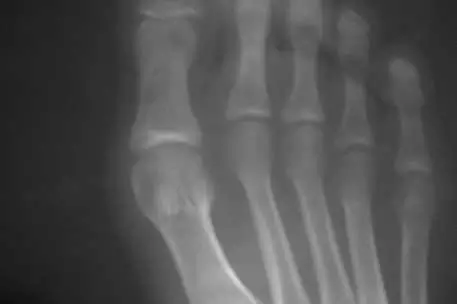

49-летний британец Стив Вебб (Steve Webb) на протяжении 29 лет ходил со сломанной ногой, сообщает The Telegraph. Вебб сломал ногу, когда попал в аварию на мотоцикле в 20-летнем возрасте. Британец все эти годы страдал от боли, но только недавно узнал, что у него сломана нога. Он прошел обследование в госпитале. Вебб испугался, что ногу ампутируют. Однако врачи заверили, что ему сделают операцию по удлинению атрофировавшейся кости на шесть сантиметров. По словам британца, это экстраординарный случай, поскольку на протяжении этих лет врачи говорили ему, что нога зажила и перелома нет. Вебб ходил с металлической пластиной в ноге, а в прошлом году почувствовал резкую боль. Когда пластину убрали, то выяснилось, что кость все еще сломана. Шансы на успех операции, которую проведут в ортопедическом центре Наффилд (Nuffield) в Оксфорде, составляют 99 процентов. Man had broken leg for 29 years - The Telegraph, 15.06.2009 Больница Nuffield.